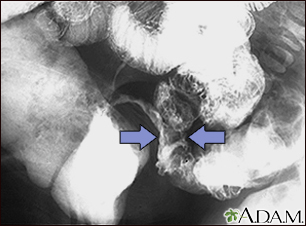

Crohn disease - X-ray